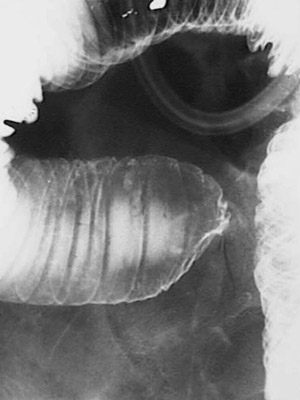

| This upper GI series demonstrates a closer view of an area of narrowing of the small intestine from an adhesion between loops of bowel that formed following abdominal surgery years before. Such "internal hernias" are the most likely cause for bowel obstruction in persons who have had previous abdominal surgery. |